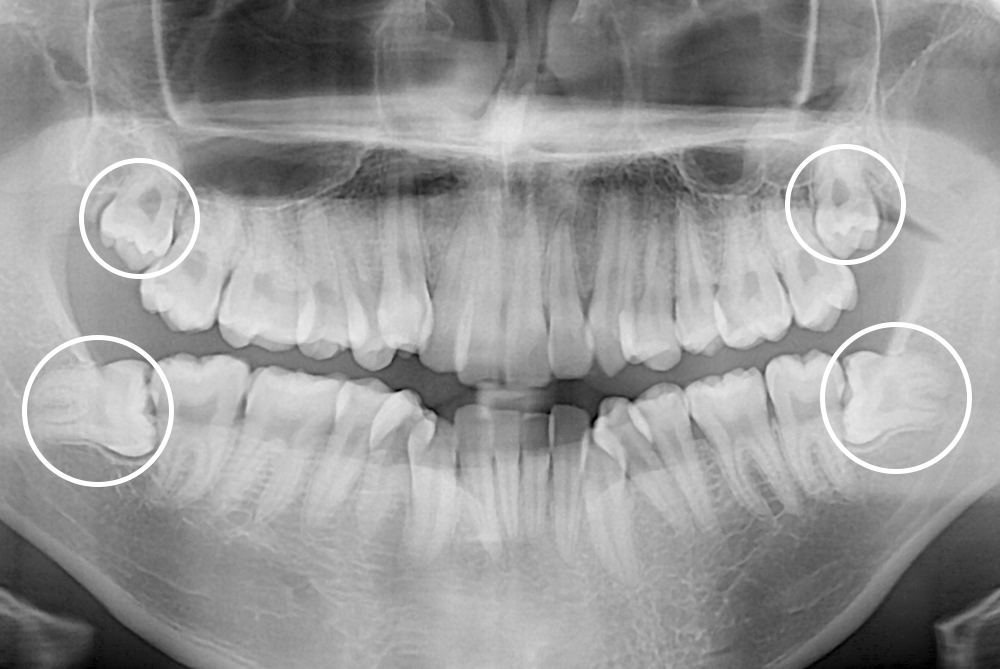

[사랑니] 매복 사랑니 발치

치료전 : 2017-03-06